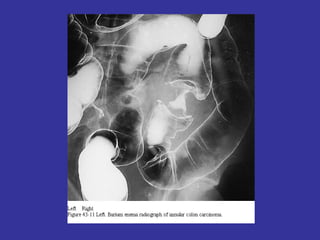

•   Estudios de imágenes: Rx tórax, Rx colon a doble

contraste, ecografía abd., TAC abd. Eco-endorrectal.